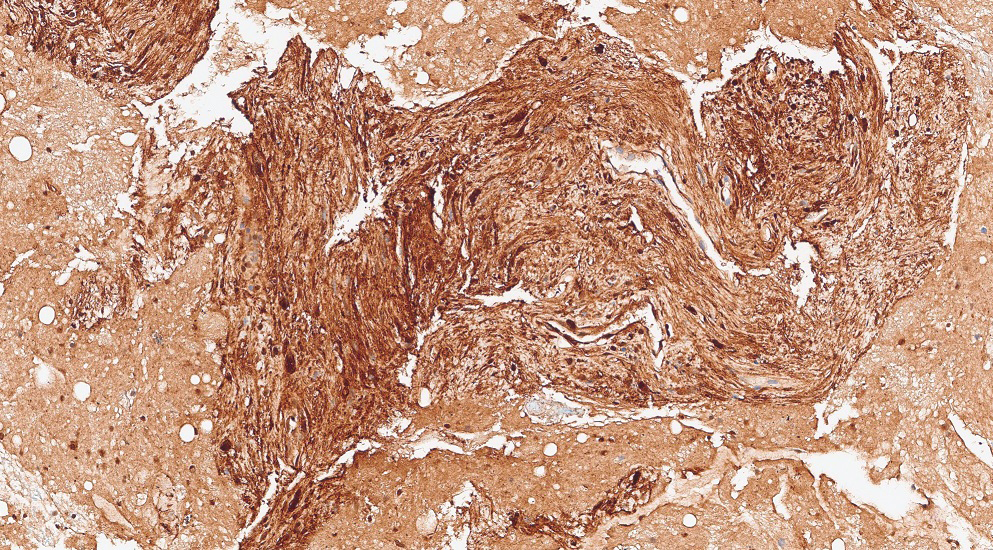

Figure 6: Cell block, S100 immunocytochemical stain

The FNA aspirate smears (Figure 1 to 4) show clusters of spindle shaped cells arranged in short fascicles with pale eosinophilic cytoplasm, and slender wavy or buckled nuclei. No significant nuclear atypia, mitotic activity or necrosis was identified. Variable amount of collagenous material separates these spindle cells. The cell block (Figure 5) shows cohesive tissue fragments, with fibrillary stroma and focal palisading of the spindle, wavy, or fish-hook–like nuclei with pointed ends. The spindle cells show fine chromatin, smooth and regular nuclear membranes, and inconspicuous nucleoli and bipolar spindle cytoplasm. Immunocytochemical stain performed on the cell block reveals that spindle cells are positive for S-100 (Figure 6). The cells also showed nuclear positivity for SOX-10, while they were negative for cytokeratin AE1/3 and CAM5.2, CD68, CD34, CD117, DOG1, ERG, MelanA, and HMB45 (Not shown).

All schwannomas show diffuse nuclear and cytoplasmic staining for S100, particularly in Antoni A (Cellular) areas. SOX10 nuclear staining is usually extensive. GFAP and CD34 staining is variable. Mediastinal schwannomas can show patchy staining for cytokeratin AE1/AE3. Table 1 highlights the characteristic ICC in other spindle cell lesions in differential diagnosis.